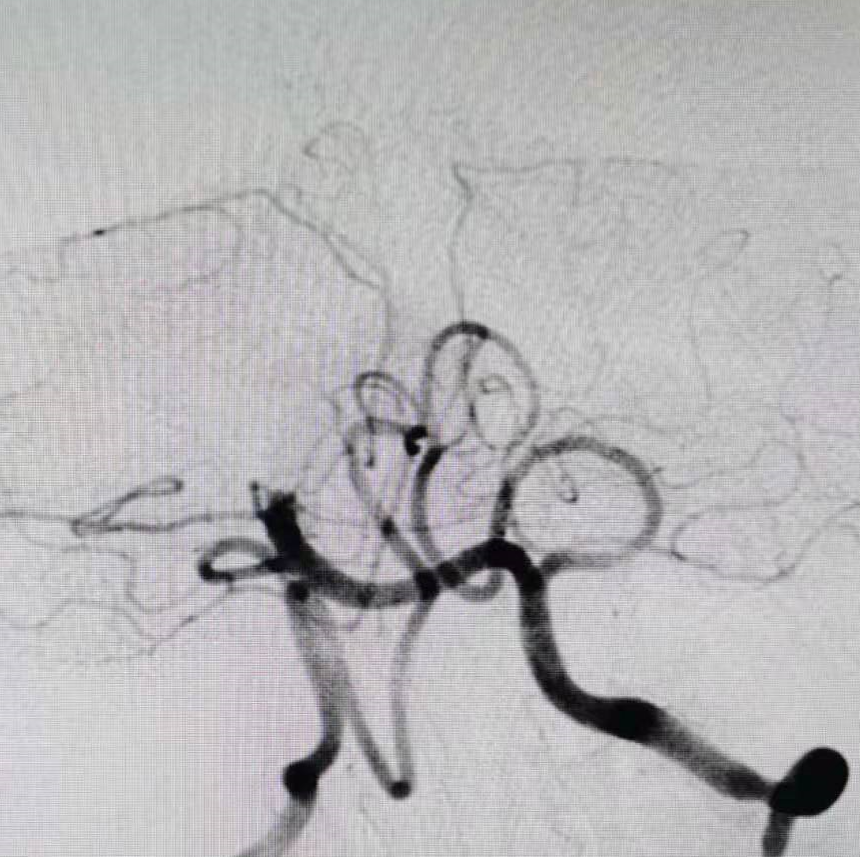

全脑血管造影提示右侧椎动脉颅内段闭塞,左侧椎动脉颅外段走形迂曲,基底动脉近端闭塞。

颈动脉造影示后交通开放。

5F 115cm远端通路导管超选至左侧椎动脉V2段,选取术中工作角度造影。

通过微导丝微导管技术,0.014in微导丝通过闭塞血管,将Rebar 18微导管管头置入基底动脉中段,微导管内造影确保在血管真腔内。

通过长交换技术保留transend微导丝,将加奇SacSpeed® 2.5mm×9mm颅内球囊,放置在基底动脉闭塞部位。

8atm压力扩张闭塞部位。

扩张后造影,提示恢复正向血流,残余狭窄50%左右。发现加奇SacSpeed® 2.5mm×9mm颅内球囊扩张部位存在双腔征,考虑血管夹层,给予替罗非班8ml/h持续泵入。

观察5分钟后再通血管闭塞。

同样方法给予9atm压力再次扩张闭塞部位。

通过长交换技术,将XT-27定位在右侧大脑后动脉P2段,将Neuroform颅内支架3.5×15mm,定位在基底动脉狭窄处。

释放支架。